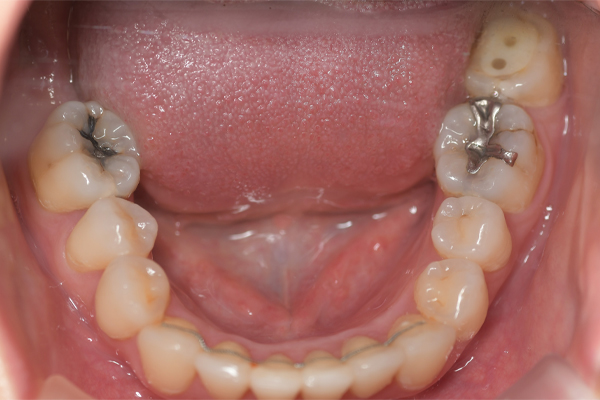

| 担当医 | 白須先生 |

|---|---|

| 年齢・性別 | 30代・女性 |

| 主訴 | 右下7番の歯がないところを治療したい |

| 治療内容 | 右下7番のインプラント治療 |

| 治療費 | 【合計】671,000円 【内訳】 診断料55,000円 静脈内鎮静法77,000円 サージカルガイド55,000円 骨造成110,000円 埋入料165,000円 2次オペ22,000円 上部構造(フルジルコニア)187,000円 (2025年1月現在時点) |

| 治療期間 | 6ヶ月 |

| リスク・副作用 | インプラント埋入は外科的な処置であるため、一過性、場合によっては持続的に知覚鈍麻が起こる可能性があります。 インプラント体と骨との結合が半年では十分にすすまないことがあります。その場合は治療期間が伸びることがあります。 外科処置後、痛みや腫れといった症状が約1~2週間程続きます。内出血がでることもあります。 |

| 術前 | 途中経過 | 術後 | ||

|---|---|---|---|---|

![]() |

途中経過 | ![]() |

術後 | ![]() |